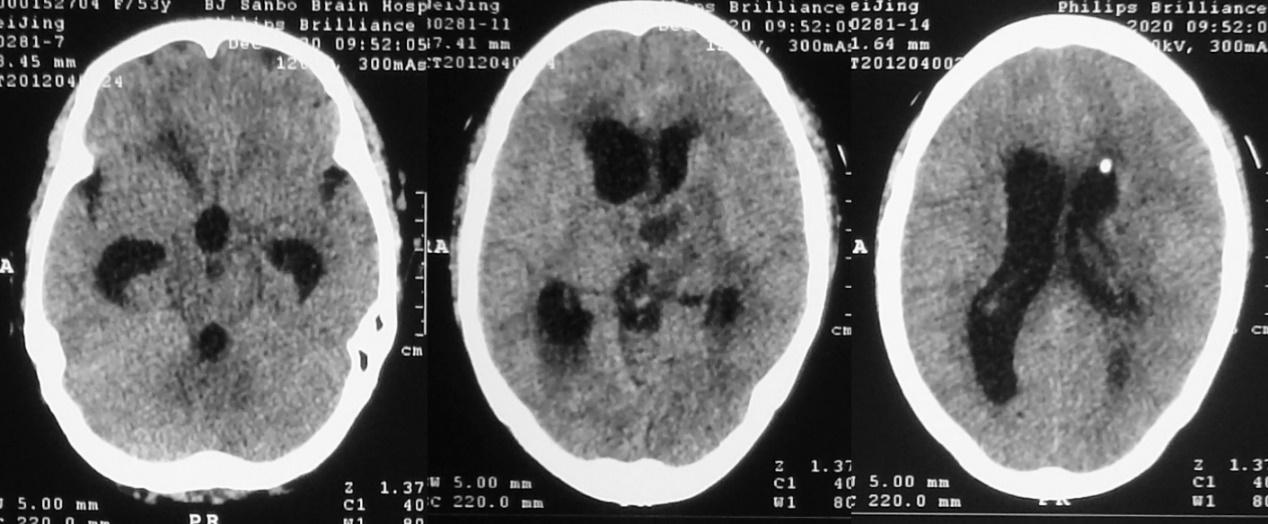

发病后21天,脑室外引流后8天,即2020年11月29日,复查头颅CT见左侧脑室较前(2020年11月22日)缩小( 图-6 ),继续抗炎及脑室外引流治疗。

图-6: 2020年11月29日头CT